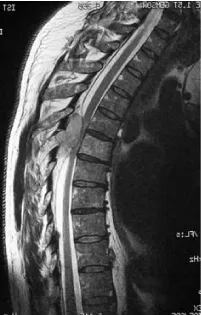

This is a retrospective study where 124 patients from January 1st, 2000 to May 31st, 2015, affected by multiple myeloma with vertebral localisation were included. All the patients were operated at a single centre by senior surgeons belonging to a single unit. Demographic details like age, sex were noted. All patients, before the surgery, were studied with standard X-ray, bone scan, CT and MRI (Figures 1,2) of the spine and location, number, type of lesions were noted. Laboratory tests including serum immunoelectrophoresis and the Bence-Jones protein urine/blood test were also done. They were clinically assessed prior to surgery and patients were divided into those presenting with only pain, radicular symptoms and neurological deficit. Visual Analogue Scale (VAS) was used and the scores were categorised into mild, moderate and severe. Written and informed consents were taken regarding the surgical procedure they underwent. Intra and post operative complications, if any, were noted.

Particularly interesting and surgically challenging was a case of G.E., male, 64 years old. In 2012 this patient underwent a stabilisation of the levels included from T7 to L3 and decompression at T8-T9 and L1-L2 for cauda equina syndrome following a pathologic fracture with cord compression. In 2014 he presented to our outpatient clinic for regular follow up with hyperkyphosis secondary to new pathologic fracture of L3, which was the level lower to the most caudal vertebra previously instrumented, associated with additional new pathologic fracture of T6, T9, hardware mobilisation, and skin decubitus ulcer. He, therefore, underwent a new surgical intervention for hardware removal, vertebroplasty at T6, T9 and L3 and consecutive L1 corpectomy, deformity correction and reconstruction of the L1 vertebral body with autologous bone graft and lateral plate T12-L2. After 12 months from the second surgery hyperkyphosis and skin ulcers in the site of hardware, decubitus were still present. We met 2 minor complications (Grade I [20,21]) not directly correlated to the surgical intervention: a transient dysphonia and a case of intraoperative hyperthermia.